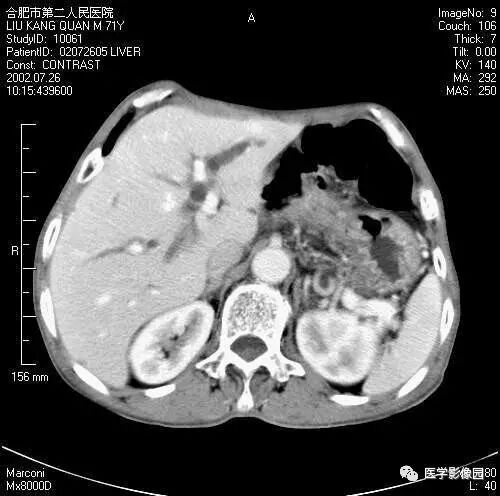

图6-4-13胰腺癌

CT平扫见胰体、尾部局限性肿大,

其内境界不清的低密度灶(↑);

肝右叶有多个低密度转移灶(长↑),

并见腹水